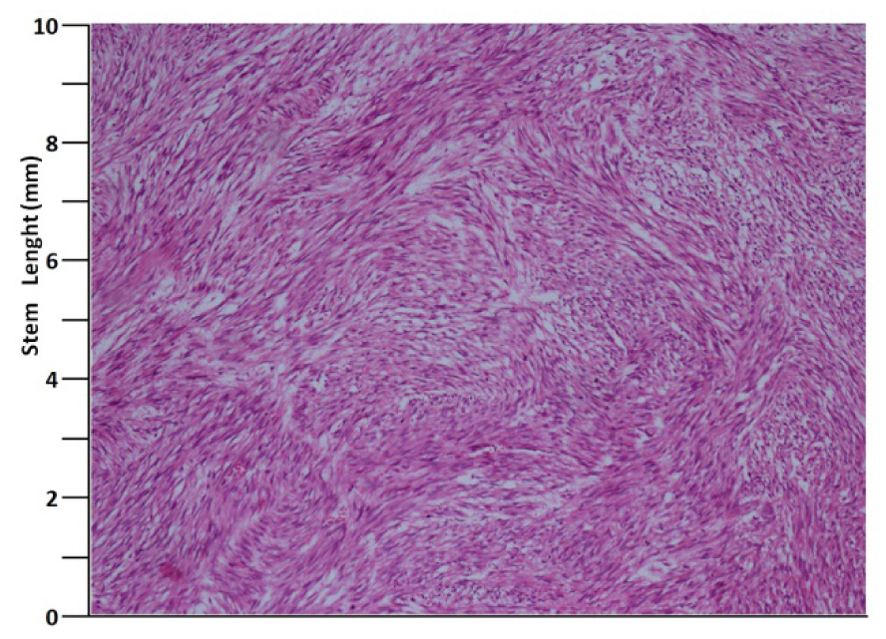

A 41 years old man presented with low urinary tract symptoms lasting for 8 months and progressing steadily. Percutaneous cystostomy catheter was inserted to the patient who could not be catheterized via transurethral route. His laboratory investigations were as follows: hepatic function tests and alkali phosphatase normal; urea: 51 mg/dL; creatinine: 1.48 mg/dL; complete urinary analysis: plenty of erythrocytes and 3 - 4 leukocytes per field; no growth in the urine culture. PSA was measured as 0.7 ng/mL. The prostate was palpated as diffusely hard in the digital rectal examination. The patient underwent palliative transurethral prostatic resection. On the endoscopic view, the crista urethralis, verru montanum and prostatic urethra had irregular anatomy and the prostatic urethra appeared to be obliterated due to presence of tumor. Macroscopically, 25 cc of tissue was resected. Pathologic examination revealed high-grade spindle cell sarcoma of the prostate and widespread mitosis and necrosis in 8 of 10 magnification fields (Fig. 1, 2). In immunohistochemical examination presence of actin, vimentin, desmin, CD34, S100 and PR was examined. Diagnosis of spindle cell leiomyosarcoma was made (Fig. 3). PET/BT scanning revealed widespread lung metastases. Adjuvant chemotherapy was scheduled.

![]() Click for large image | Figure 2. H&E, × 100. |